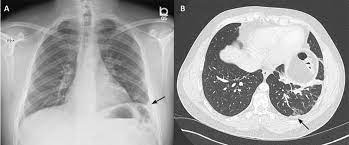

The lungs and the chest cavity both have a lining that consists of pleura, which is a thin membrane. A pleural effusion means there is fluid in that chest cavity. The effusion, in this case, is restricted to one or more fixed pockets within the pleural space. Ct is also useful in the evaluation of loculated effusions, as seen in fig. Multiloculated means that the fluid isn't just one single continuous collection but loculated pleural: Understanding pleural effusion pleura refers to thin membranes that line the lungs and the inside of the chest cavity. Finally, there might a large, loculated pleural effusion caused by bacterial pneumonia or tuberculosis which may require surgery because it can thicken into. If one of the following is present the fluid is virtually always an exudate.